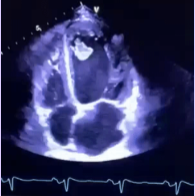

Rhabdomyoma

What is seen in this TTE?

<p>What is seen in this TTE?</p>